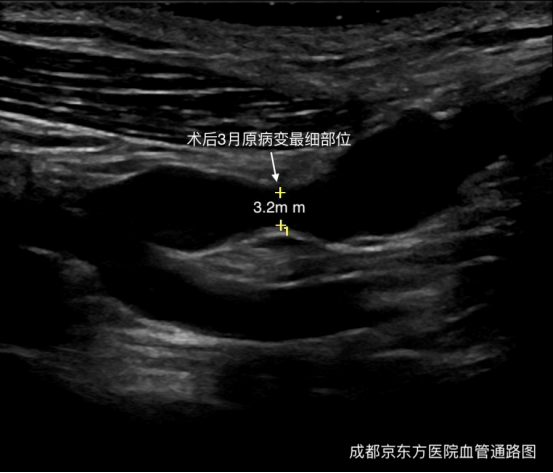

检查发现:我们这位患者有一个大吻合口、单一回流途径、血透龄超过 3 年的自体动静脉内瘘,这也是头静脉弓常见病变原因。成都京东方医院血管通路 MDT 团队经讨论采用了目前治疗首选方法超声引导下 PTA(经皮腔内血管成形术)。穿刺入路为同侧上肢通路静脉,使用 0.035 超滑导丝顺行通过头静脉弓狭窄,采用逐级扩张策略行球囊扩张。术后震颤增强,血流量:240 ml/min,高通量透析器,透析 4 小时,kt/v:1.41,URR:69.7%。